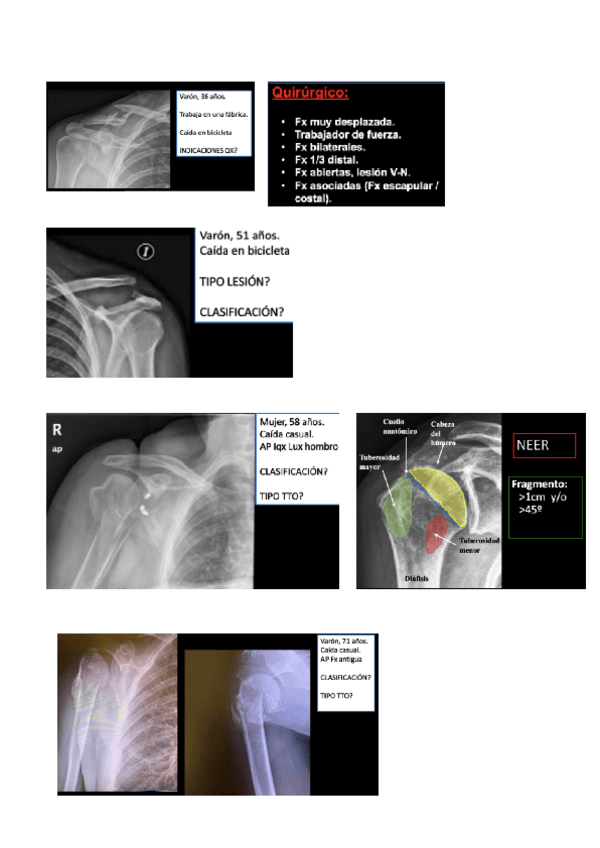

RADIOGRAFIAS PAT.QUIRURGICA

He publicado nuevos apuntes de 2º Patología Quirúrgica: RADIOGRAFIAS PAT.QUIRURGICA

rx-2.pdf

rx-1.pdf